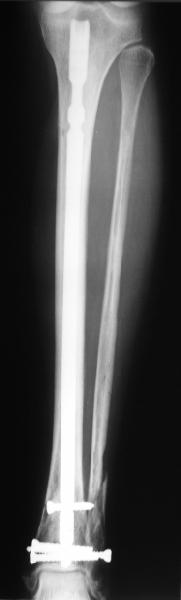

At least both the ankle mortise and tibial alignment look acceptable, don't they?

I am just trying to illustrate that prevention of 1)tibial valgus and 2)loss of reduction can be provided without fibular plating. Small changes of conventional nailing techniques allow to maintain reduction of the tibia reliably without adjunctive fibular stabilization.

In delayed cases acute length restoration performed only in the tibia may leave the fibula shortened thus change the mortise. So it is reasonable to restore length of both bones simultaneously by distractor and fix the fibula not with open reduction and plating but just by a single perQ screw. Example attached.